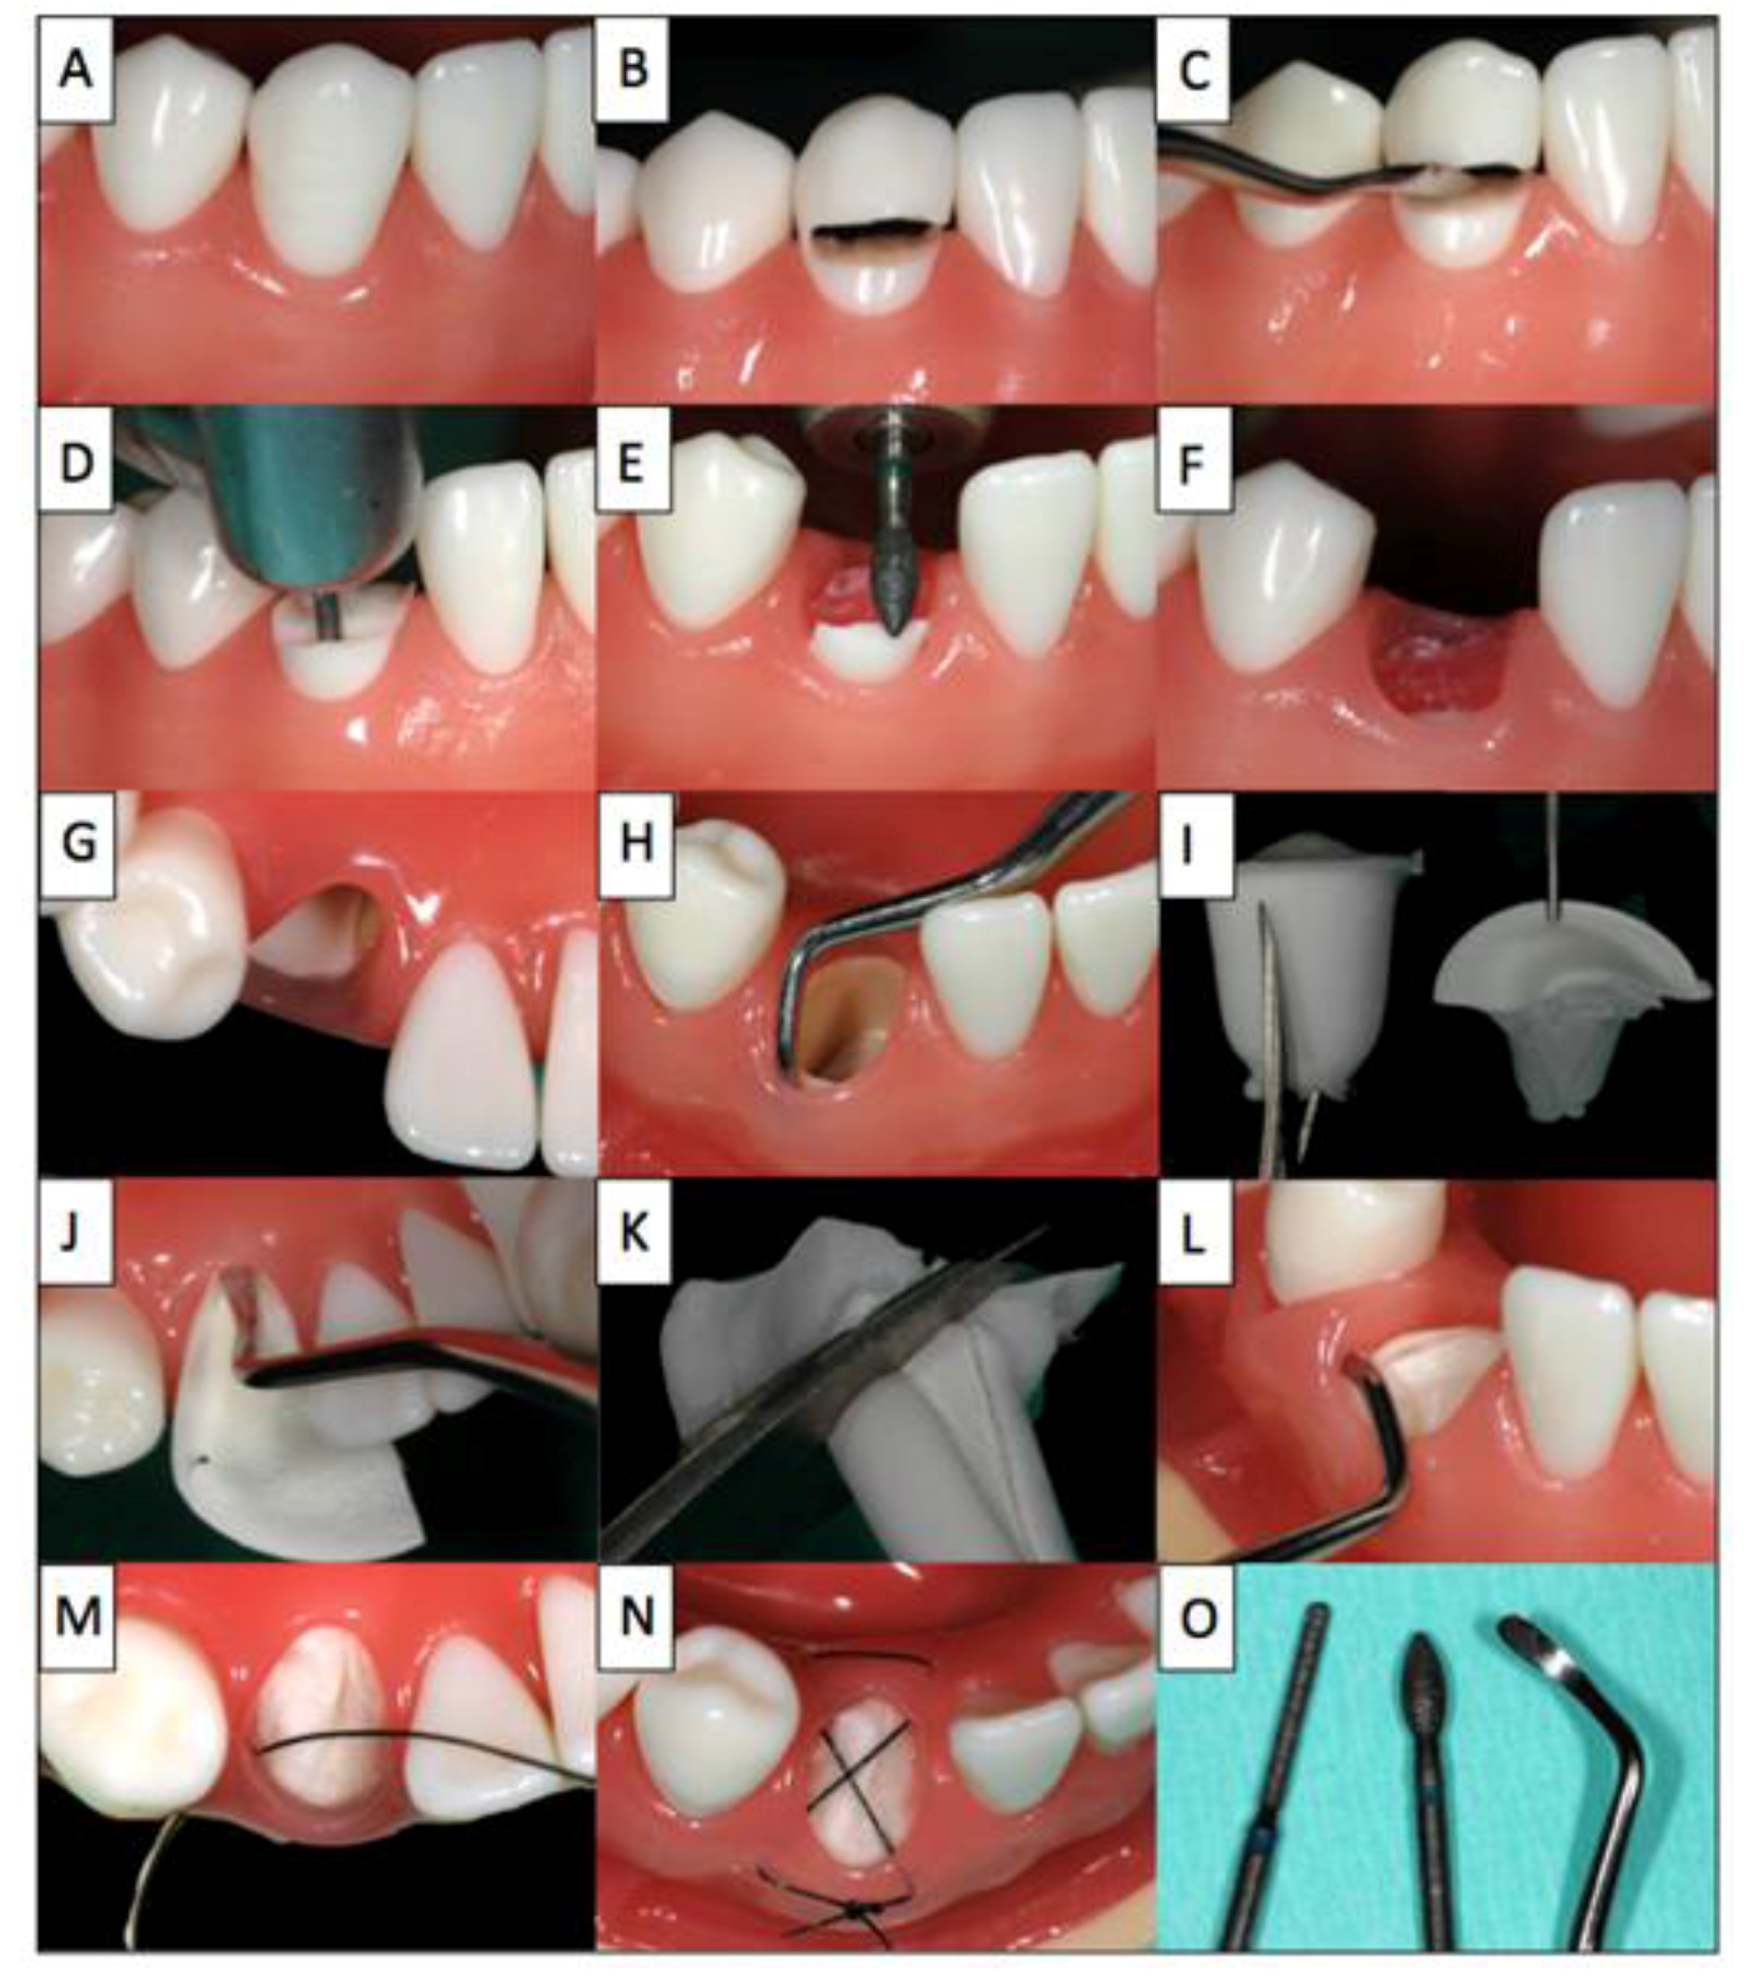

A step-by-step illustration of the proposed procedure using a model illustrating the extraction and treatment of tooth 43 is given in Figure 1:

Figure 1. The step-by-step procedure illustrated on a model (Frasaco GmbH, Tettnang, Germany).

Dentistry 02 00011 g001

Firstly, the hopeless tooth is split supragingivally (B) and the crown fragment is carefully dislocated and removed using a suitable instrument (C). Then, the root is separated vertically in a ratio between 1:3 and 2:3 (D). The smaller, buccal root fragment is retained and the larger lingual root fragment is removed in a manner that spares bone and soft tissue to the greatest possible extent. The height of the buccal socket shield is reduced to the level of the bone (E,F) and the gingiva overlying the retained buccal root fragment is tunnelled by 2 mm (H) to allow the insertion of the collagen cone (I,L) into the tooth socket and placement of the membrane part of the collagen cone under the buccal mucosa. Finally, the collagen cone is secured with a criss-cross suture (M,N). For this intervention, only the following instruments are required: periotome, Black’s excavator, gingival scissors, needle holder and surgical forceps as well as diamond drill (O). After the procedure, patients rinse with 0.2% chlorhexidine mouthwash two to three times daily for one minute over a period of at least ten days. During this time, mechanical oral hygiene is avoided in the affected area and only restarted after the follow-up examination and suture removal after ten days. Anti-inflammatory drugs (e.g., Mefenacid 500mg tid) are prescribed as needed. Typically, no antibiotics are prescribed (exemption: systemic diseases, shielding etc.). Each patient was informed verbally and in writing about the treatment and the materials used as well as the associated pre- and post-operative risks and gave their written consent to the use of the collected data and photos.